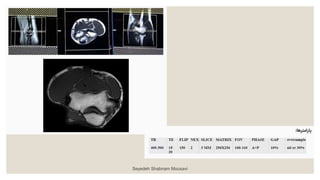

◦ ‫آگزیال‬ T1W ‫ضخامت‬ ‫با‬ ۳ ‫میلیمتری‬ : ◦ ‫به‬ ‫و‬‫بورونال‬ ‫صدحه‬ ‫رو‬ ‫را‬ ‫آگزدال‬ ‫مقاطع‬ ‫و‬ ‫داخلکی‬ ‫برککدل‬ ‫اپکی‬ ‫از‬ ‫بکه‬ ‫خطکی‬ ‫موازات‬ ‫بچیریک‬ ‫گذرد‬ ‫می‬ ‫خارجی‬ . ‫را‬ ‫مقکاطع‬ ‫موقعیکت‬ ‫بریک‬ ‫چک‬ ‫نیز‬ ‫ددد‬ ‫صدحه‬ ‫دو‬ ‫در‬ . ‫صکدحه‬ ‫در‬ ‫اساخوا‬ ‫به‬ ‫ومود‬ ‫مقاطع‬ ‫بریک‬ ‫چک‬ ‫ساجیاال‬ ‫باشرک‬ ‫بادک‬ ‫ساوک‬ ‫و‬ ‫بازو‬ . ‫هکا‬ ‫ش‬ ‫بک‬ ‫تعکاد‬ ‫تکا‬ ‫فوسا‬ ‫انو‬ ‫اوسن‬ ‫از‬ ‫باالت‬ ‫ش‬ ‫ب‬ ‫دو‬ ‫بادک‬ ‫راددکال‬ ‫وزداه‬ ‫توب‬ ‫از‬ ‫ت‬ ‫پادی‬ ‫مقطع‬ ‫دو‬ ‫دهک‬ ‫پوشش‬ ‫را‬ . ‫و‬ ‫باال‬ ‫در‬ ‫اشباع‬ ‫بانک‬ ‫گذاشا‬ ‫وق‬ ‫وک‬ ‫پاسسیشک‬ ‫آرتیدنکت‬ ‫از‬ ‫مقکاطع‬ ‫پادی‬ Seyedeh Shabnam Mousavi